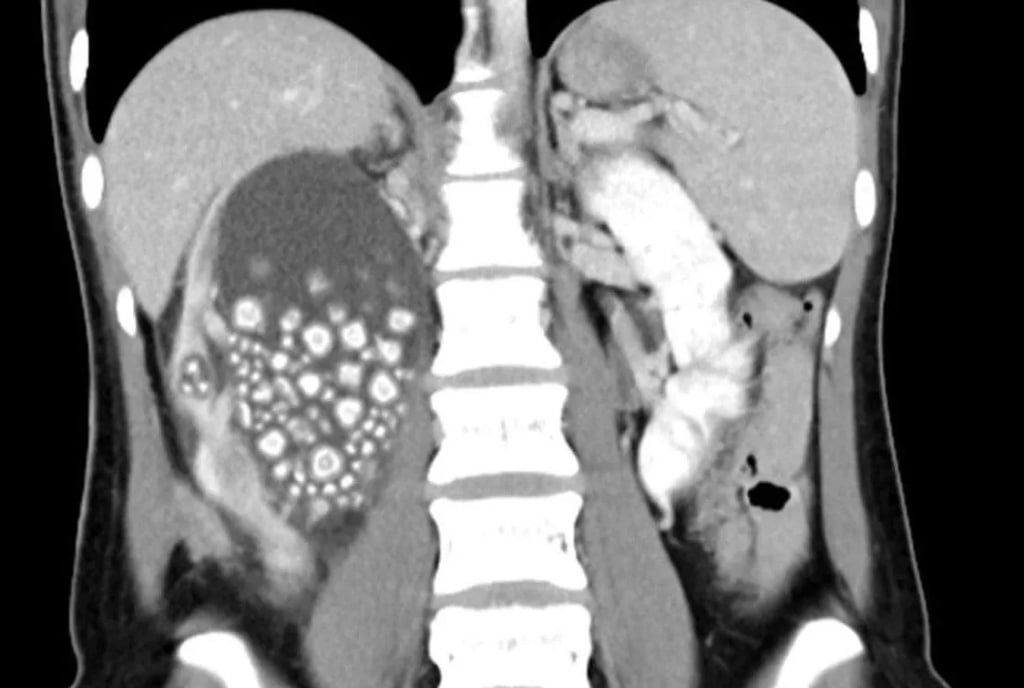

Девушке с Тайваня удалили больше 300 камней из почек 😀

По словам врачей, всё из-за частого потребления сладких напитков — сверхразумша пила в основном только холодный чай из магазина вместо воды.